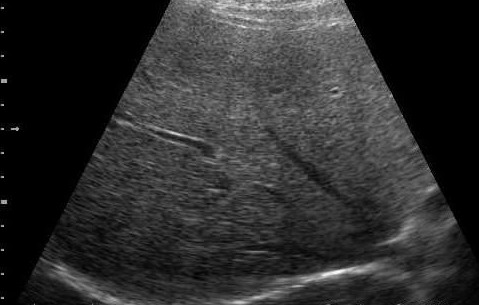

那么到底肝脏里面有没有脂肪呢?这一点医学早就证实:人体都是由细胞组成的,肝脏也是由一个一个肝细胞构建起来的,在每一个细胞里,都含有必不可少的构成细胞的基本成份或者是物质、材料,那就是蛋白质、脂肪、糖,所以每个肝细胞都会有脂肪存在,只是因人而宜,脂肪在肝细胞里的含量多少不同而已。脂肪肝(fatty liver)是指各种原因引起的肝细胞内脂肪堆积而言。正常人每100克肝脏湿重约含4~5克脂质。目前医学上确定的标准是:肝细胞里含有的脂肪在5%以下,被列为正常;如果含量在30%以上,可以称为肝的脂肪变性,或者是脂肪堆积,才称为脂肪肝。那么脂肪肝的证实、明确,不是靠超声、CT、核磁,不是靠这些影像学的方法来判断肝细胞里有多少脂肪,仅靠影像学的所见诊断脂肪肝是不准确的。就拿超声检查来说,正常肝与脂肪肝的区别不是那么可靠的。(图1、2)

图2 脂肪肝的超声图像